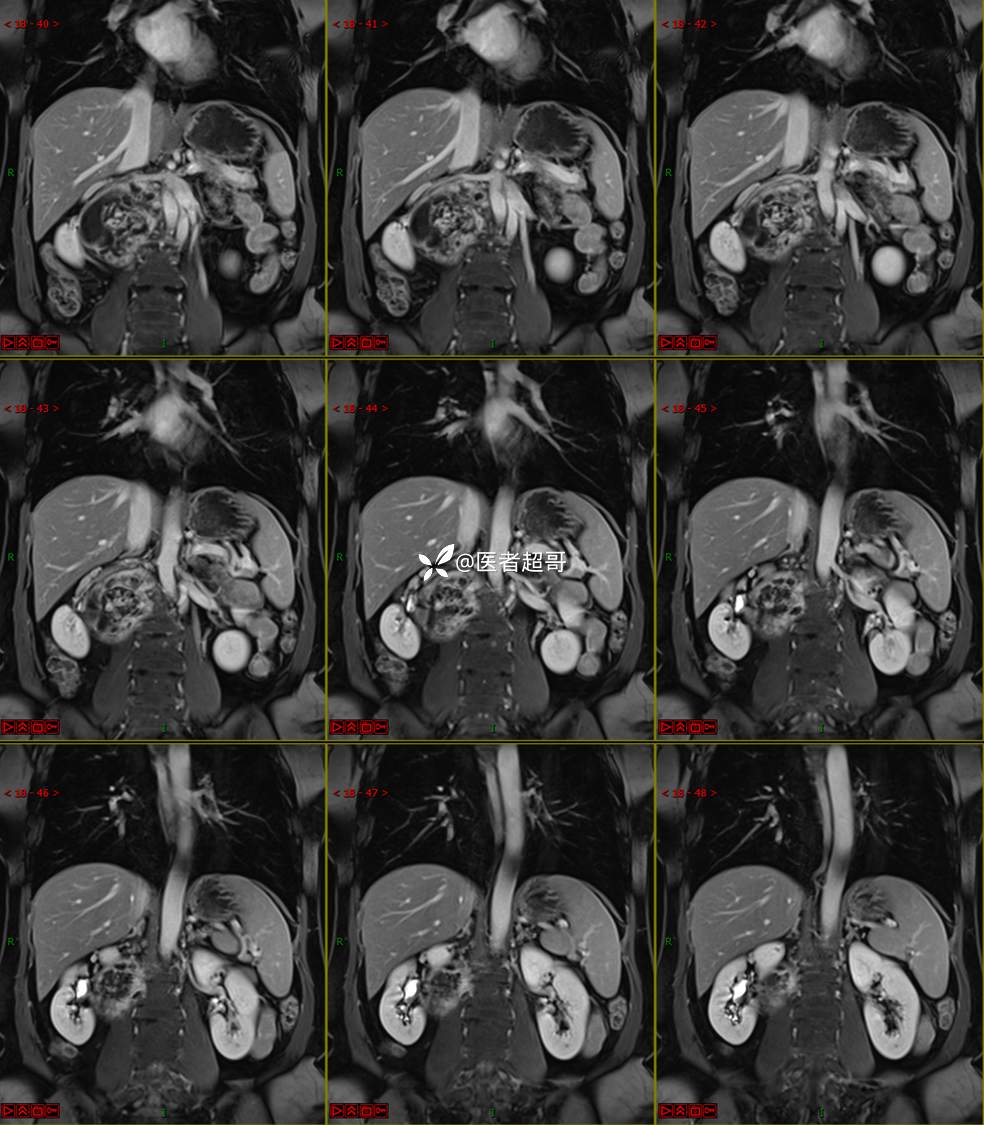

【影诊笔记671】定位有难度,究竟是腹腔内or腹膜后,请先定位,再定性!有结果~~~

专科检查:腹部平坦,腹肌软,无压痛及反跳痛,无包块,肝脾无肿大,Murphy征阴性,腹部叩鼓,肝脾双肾无叩痛,移动性浊音阴性,肠鸣音正常。我院 肝胆胰脾肾彩超提示:脂肪肝、腹腔内囊实性团块,建议进一步检查。